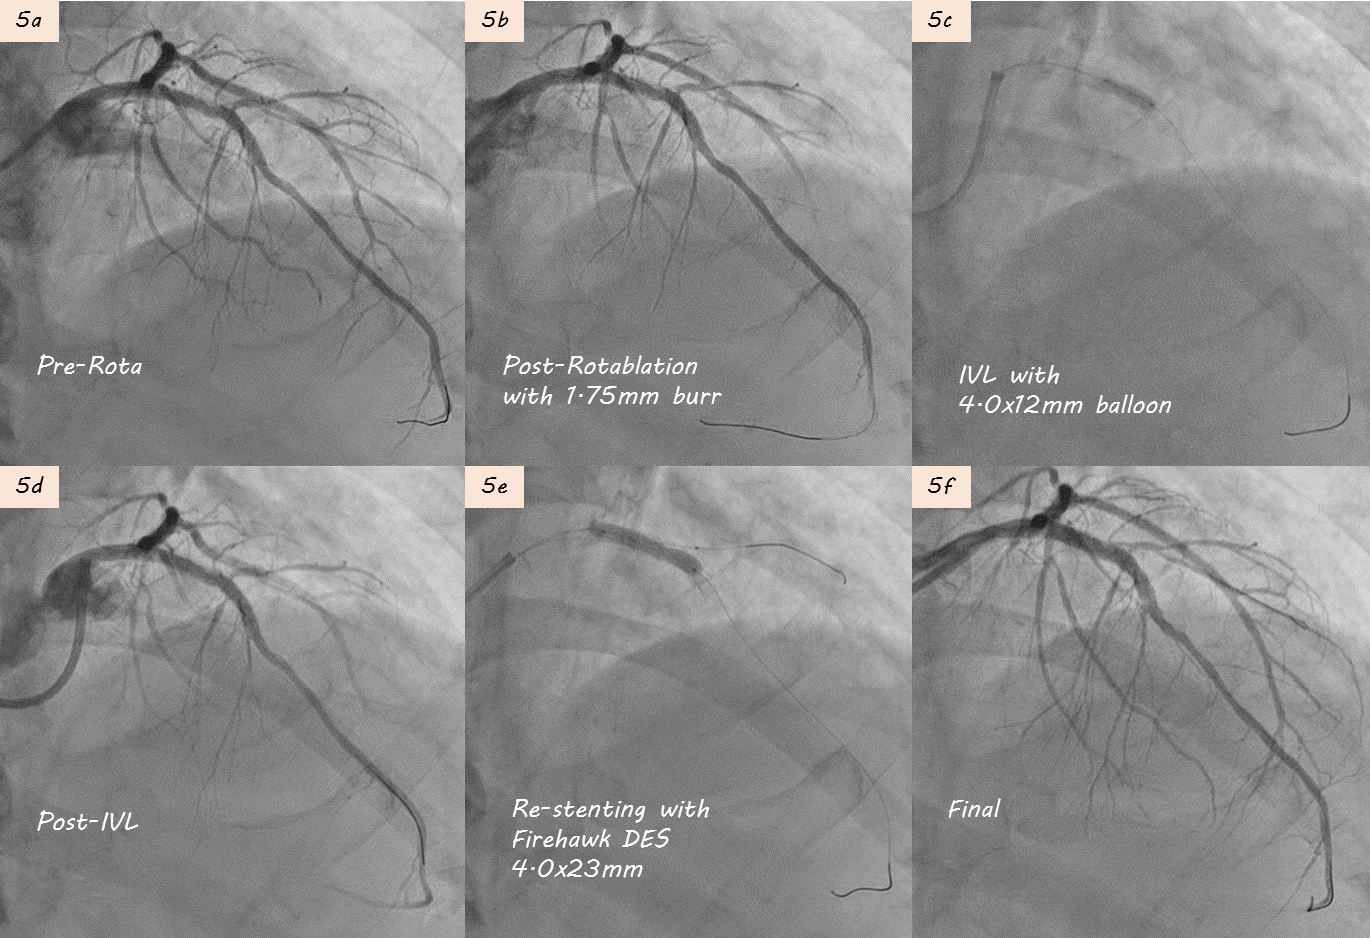

During 1st PCI, IVUS showed severe calcification in LAD seg6 (Fig. 2a). Rotablation with a 2.0 mm burr was performed (Fig. 2b), and a 3.5¡¿28mm Multi-Link BMS was implanted but remained underexpanded (Fig. 2c).STEMI developed one week later prompted repeat CAG showing subacute thrombosis within LAD stent (Fig. 3a). Thrombus aspiration was performed. POBA with a 3.5¡¿15mm Raiden balloon (up to 24 atm) failed to fully expand the stent (Fig 3b). Subsequently, a 3.5¡¿30mm MagicTouch DCB was used.During 3rd PCI,rotational atherectomy was performed with 1.75mm and then 2.0mm burrs; however, 2.0 mm burr entrapment occurred during lesion crossing, and angiography showed limited debulking effect (Fig 4a-b). High-pressure balloon with APT NC 3.5x12mm were attempted but rupture(30 atm). We then POBA with Raiden 3.5¡¿15mm (30 atm), Raiden 4.0¡¿15 mm (32 atm), and NC Euphora 4.5¡¿15mm (20 atm). Finally, 4.0x40mm B. Braun DCB angioplasty was performed (Fig 4c).4th PCI was performed 1 month later for intravascular lithotripsy (IVL) and new stent implantation. Second time rotablation with a 1.75 mm burr was performed (Fig. 5a-b). IVL with a 4.0¡¿12mm balloon (100 pulses) achieved adequate expansion (Fig. 5c–d). Adequate POBA were followed by final stenting using a 4.0¡¿23mm Firehawk DES (Fig. 5e). Proximal optimization technique and kissing balloon technique were performed (Fig. 5f). Serial IVUS showed better debulking after 2nd Rotablation and IVL, and adequate new stent expansion (Fig 6a-6f).